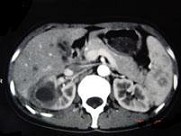

- 多项选择题女,33岁, 右肋腹痛7天,尿检可见大量的脓细胞, CT平扫+增强如图所示,下列说法正确的是 ( )

A、右肾体积增大,其内可见类圆形低密度病灶

B、增强扫描可见该病灶不均匀强化,其内有无强化的坏死灶

C、右肾病灶边界模糊不清

D、考虑为右肾囊肿合并感染

E、考虑为右肾脓肿